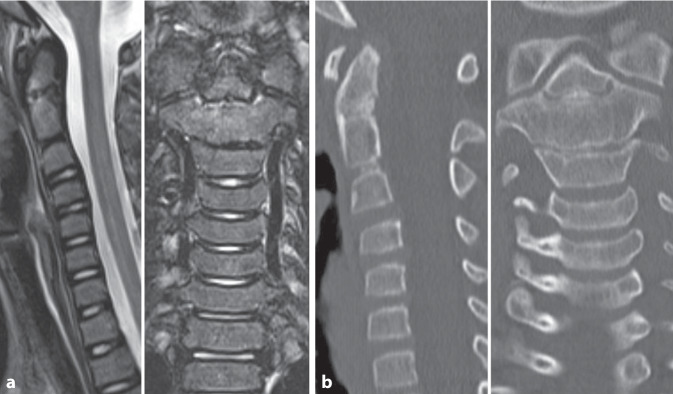

Epiphysiolysis of the dens axis is a rare injury in childhood but should be reliably investigated in the presence of typical pathological mechanisms. In our case, the injury in a four-year-old boy after a fall on his neck could not be diagnosed in the initial X‑ray. The diagnosis was made by means of an MRI scan performed during the course of the case and conservative treatment with a cervical collar was provided. The 10-year follow-up showed mild impairments, especially when remaining in a flexed position for long periods (e.g. when reading). In addition, the question arises retrospectively as to whether an additional injury to the C2/3 led to spontaneous fusion of the segment.